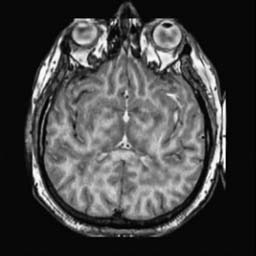

To demonstrate the effectiveness and efficiency of the proposed image fusion method , we conduct a set of comparative experiments on three image datasets. The first is composed by 8 pairs of multi-modal medical images and the second one contains 15 pairs of multi-focus gray or color natural images. These two datasets are often used in many related papers and some examples are shown in Figure 3(a) and Figure 3(b). The third one is a new multi-focus cervical cell image dataset collected by ourselves, which consists of 15 groups of color images and each group contains a series of multi-focus cervix cell images with size of or , etc. Some source examples are shown in Figure 3(c). Our source code implemented in C++ along with the new multi-focus cervical cell image dataset is available online.

We first evaluate the performance of the proposed method under varying total number of octaves and number of layers sampled per octave. The fused images of a pair of multi-modal medical images with different and are shown in Figure 4. In this example, on the one hand, when only 1 or 2 octaves are involved in constructing the DoG pyramid, the fused images fail to keep the integrity information of large size objects (e.g. eyeballs), while by increasing the value of , the integrity information of eyeballs is preserved. On the other hand, although not as significant as the increase of octave numbers , the fused image can contain more details by the increase of layer numbers . The corresponding objective quality metrics are shown in Figure 5. As shown in Figure 5(a), most of the metric values are improved as the number of octaves increases with the fixed layer numbers 3 in the global tendency and each of them tends to be stable when the number of octaves is 5. To get a relatively good quality from Figure 5(b), we can notice that some of the metric values can get a good performance when the number of layers is 3, such as the MI, SSIM, QI and VIF, though there are only a little change of all the metric values by increasing the number of layers with the fixed octave numbers 5. Because it will result in more computation burden with the increase of the value and , and for different kinds of source images, there are different performance with the diverse parameter settings. To get a trade-off between them in our experiments, we set for the multi-modal dataset, for the natural datasets and for the multi-focus cell dataset, respectively.

Figure 6 shows the fused images obtained by different methods with the multi-modal source images shown in Figure 3(a). As shown in these figures, the proposed method can produce images which preserve the complementary information of different source images well. Moreover, due to the scale-invariant structure saliency selection, our method can keep the integrity information of large size objects and the visual details simultaneously. Although the fused image generated by other methods can also capture the details to some extent, all of them fail to keep the integrity information of large size objects such as the eyeballs. Furthermore, from Figure 6(k)-6(t), the DTCWT, GFF, IM and NSCT methods may decrease the brightness and contrast while the proposed method can preserve these features and details without producing visible artifacts and brightness distortions.